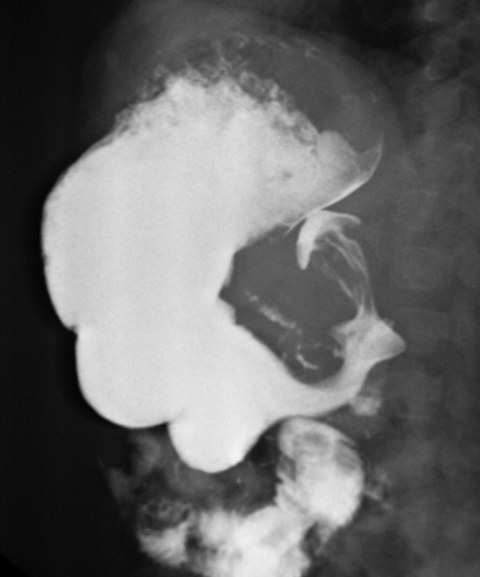

Ребёнку 1 месяц и 10 дней. Направлен педиатром для проведения рентгеноскопического исследования верхинх отделов ЖКТ. Ребёнок практически ничего не прибавил в весе, мама говорит что есть рвота.

Выполнено 2 исследования: рентгеноскопическое исследование желудка и УЗИ. Предлагаю обсудить как критерии постановки диагноза при данной патологии, так и выбор наилучщего метода диагностики:

На представленных Вами рентгенограммах желудка, на мой взгляд имеет место быть то, что у Вас называется пилоростенозом. Мы уже с Вами однажды говорили, что под пилоростенозом у нас подразумевается другое, т.е. у нас подразумевается органика, у Вас - гипертрофия сфинктера.

Хотя, как пишет Владимир Борисович такую картину может дать и кольцевидная поджелудочная железа.

Удлинён и сужен пилорический отдел желудка; на УЗИ также представлен пилорус. Я против рентгеноскопических исследований у деток при ДАННОЙ патологии, но пока, во всех руководствах, оба метода позиционируются как равные.

Да, типичная презентация гипертрофического пилоростеноза; врождённая аномалия при которой происходить хгипертрофия мышц пилоруса. Рентген признаки: удлинённый, направленный кверху пилорический канал, признак "нитки" string-sign, полоска бария в виде нити, признак двойной складки (double-fold sign).

В последнее время (лет 10), в диагностике данной патологии, на первое место выходить УЗИ. Метод прост, дёшев и весьма специфичен.

Критерии диагноза весьма специфичны и просты: толщина мышечного слоя > 3 мм. Длина канала > 12 мм. Лечение оперативное, производят миотомию. Диф. диагноз с пилороспазмом.